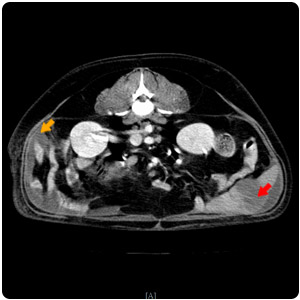

| 腎臟腫塊(紅)、腹水(黃) |

腹水(紫)、腹部腫塊(紅)、腎臟腫塊(黃) |